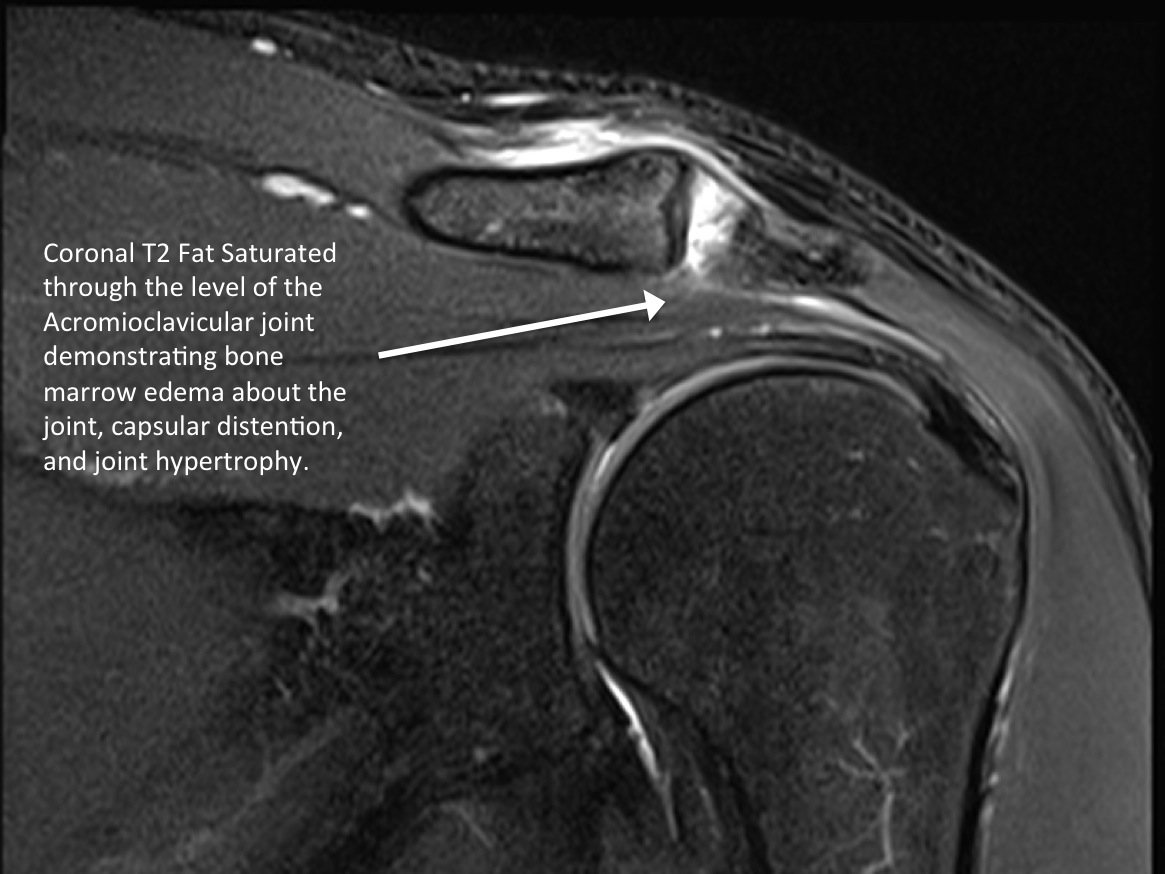

• MRI correlation